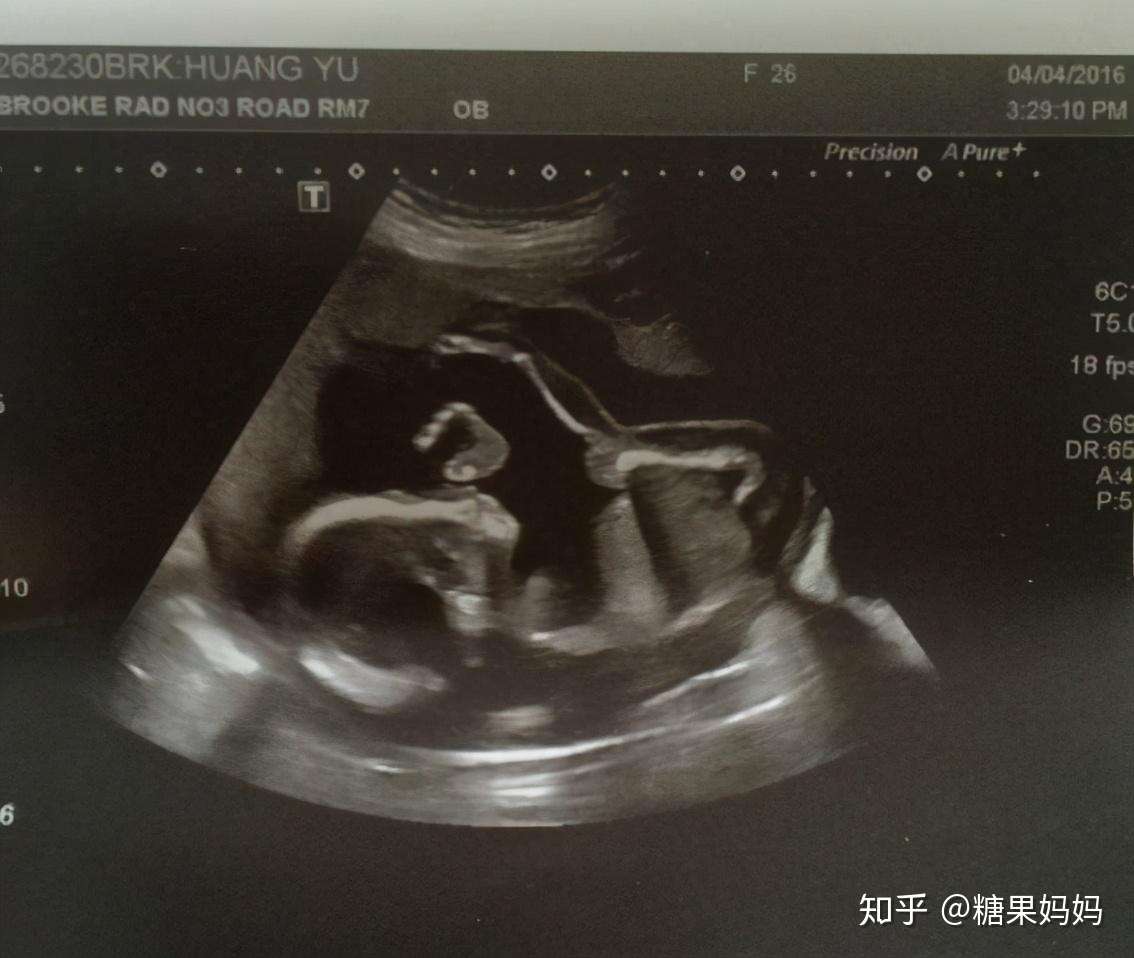

12周b超可见人形胎动了 宝宝树

12周胎动了 附12周大肚照 14年2月出生帮 妈妈帮

生命的跃动 12周宝宝的b超动态图令人惊叹 有视频哦 13年3月出生帮 妈妈帮